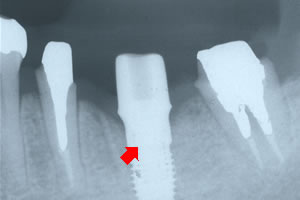

![]() レントゲン写真